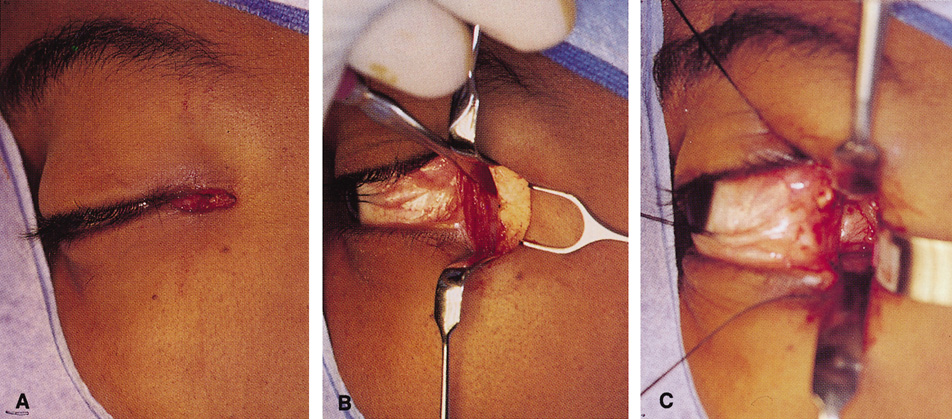

Fig. 12. A. The lateral canthotomy incision is reapproximated with simple closure

of the superior and inferior crura of the lateral canthal tendon. A drain

from the temporal fossa has been brought out through a separate stab

incision posteriorly. 12B. Excellent postoperative scar camouflage is obtained by this approach.

Fig. 12. A. The lateral canthotomy incision is reapproximated with simple closure

of the superior and inferior crura of the lateral canthal tendon. A drain

from the temporal fossa has been brought out through a separate stab

incision posteriorly. 12B. Excellent postoperative scar camouflage is obtained by this approach.